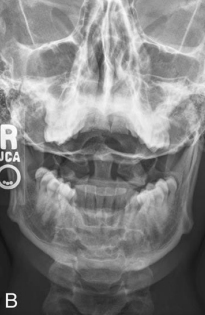

AP Open Mouth: Is this Image Good?

No.

Base of skull superimposed over dens and lateral masses

Atlantoaxial joint is not clearly demoed

Extensive extension of skull

Reposition by slight flexion of the neck or angle the CR slightly caudal